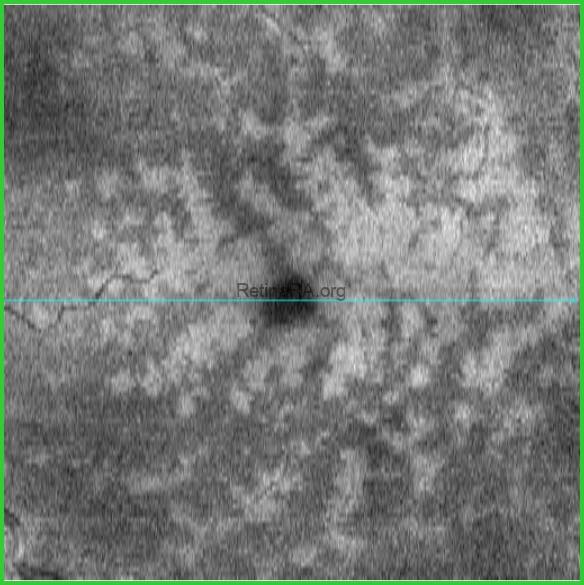

A 72-year-old male patient with Paracentral acute middle maculopathy (PAMM) and Prominent middle limiting membrane (p-MLM) sign secondary to non-ischemic (partial, incipient, Venous stasis retinopathy, etc) central retinal vein occlusion (CRVO). His visual acuity was 20/20 in the right eye and 20/50 in the left eye. Vascular tortuosity and engorgement, superficial retinal hemorrhage, and slight perivenuler whitening around fovea are seen on fundus photography (notice the difference between the two eyes). OCT B-scan shows hyperreflective band-like PAMM lesions and p-MLM sign. En-face OCT demonstrates perivenuler fern-like pattern of PAMM lesions.

En-face OCT of Non-ischemic CRVO + PAMM